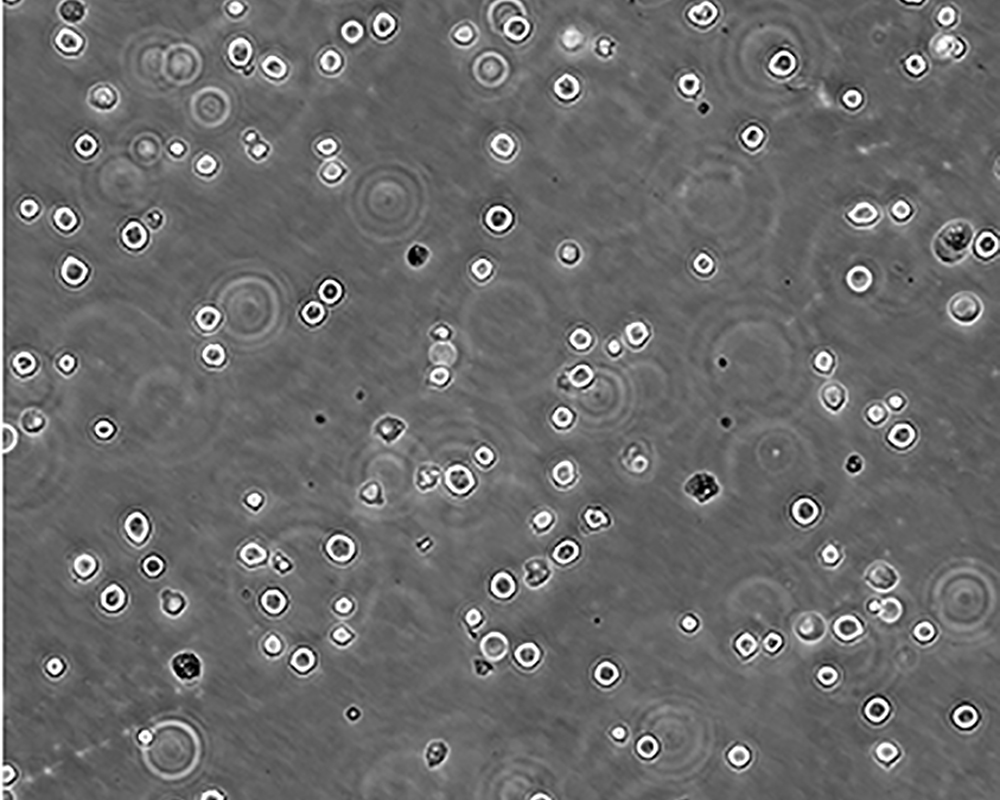

生長特性 suspension

形態(tài)特征 lymphoblast

細胞描述 The cell population has been characterized as highly undifferentiated and of the granulocytic series. Studies conducted by Anderson, et al. , on the surface membrane properties led to the conclusion that the K-562 was a human erythroleukemia line. K-562 blasts are multipotential, hematopoietic malignant cells that spontaneously differentiate into recognizable progenitors of the erythrocytic, granulocytic and monocytic series. The effect of inducers on sublines derived from the original K-562 cell line have been reviewed by Koeffler and Golde. Karyological studies on various K- 562 sublines have been classified into three groups(A,B,C) by Dimery, et al. The strain obtained by the ATCC most closely resembles the B population. Occurrence of the Philadelphia chromosome, however, was of much lower frequency; none detected in 15 metaphases examined. The line is EBNA negative.